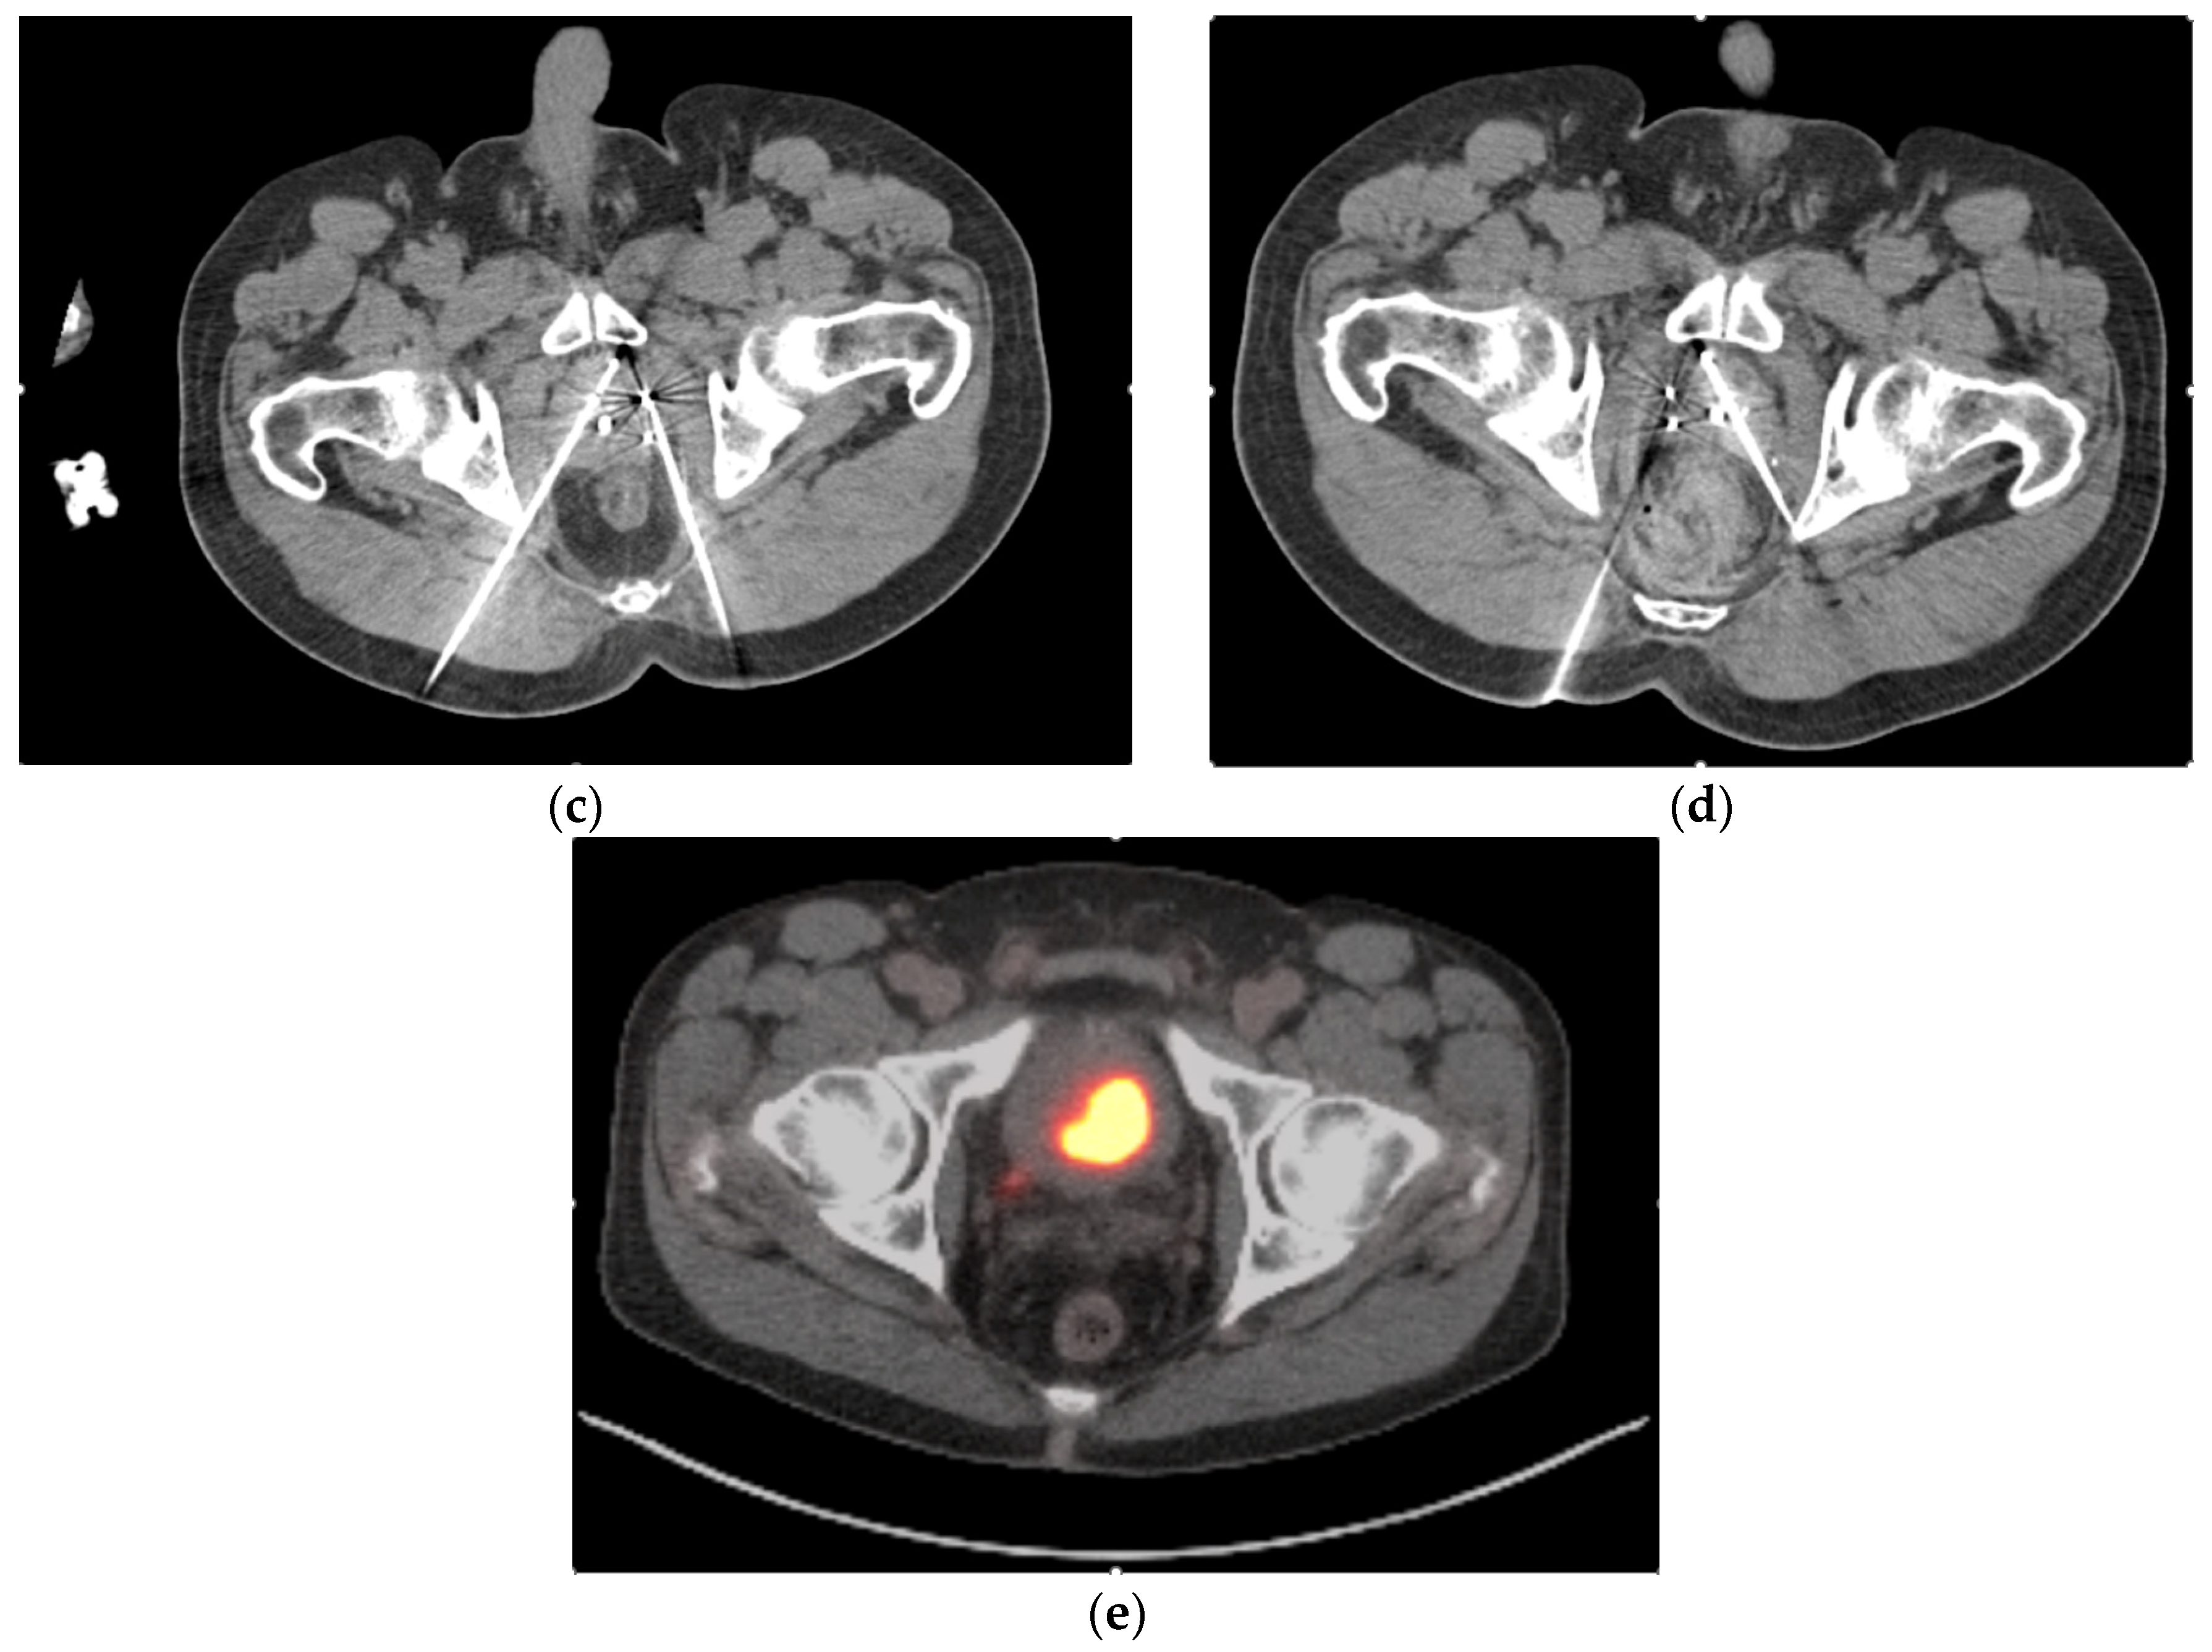

- Gangi, A.; Tsoumakidou, G.; Abdelli, O.; Buy, X.; de Mathelin, M.; Jacqmin, D.; Lang, H. Percutaneous MR-guided cryoablation of prostate cancer: Initial experience. Eur. Radiol. 2012, 22, 1829–1835. [Google Scholar] [CrossRef] [PubMed]

- Bomers, J.G.; Yakar, D.; Overduin, C.G.; Sedelaar, J.P.; Vergunst, H.; Barentsz, J.O.; de Lange, F.; Fütterer, J.J. MR imaging-guided focal cryoablation in patients with recurrent prostate cancer. Radiology 2013, 268, 451–460. [Google Scholar] [CrossRef]